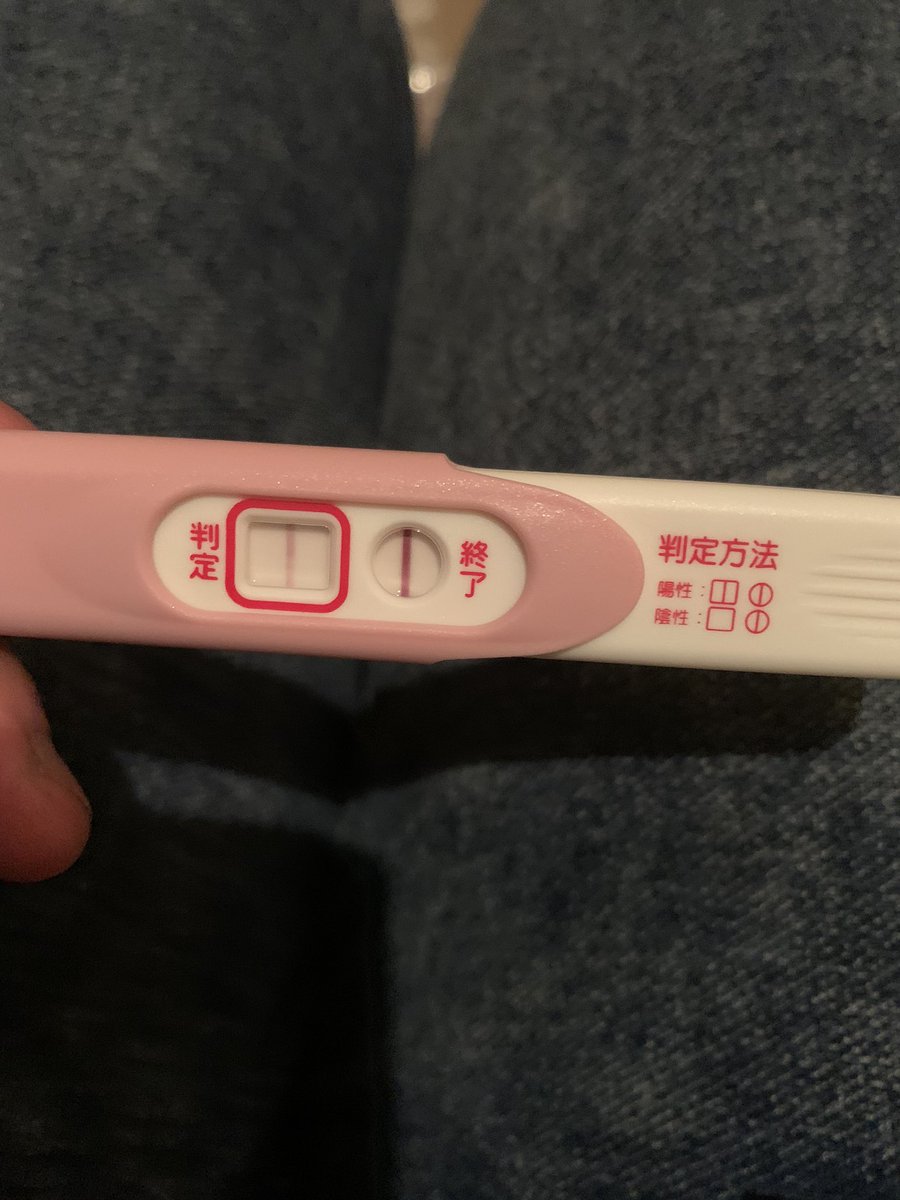

妊娠検査薬 画像 陽性-Jan 21, 21 · 医師監修妊娠検査薬の判定窓に薄い線が出ることがあります。「この線は陽性?それとも蒸発線?」判断に迷ったことはありませんか?そこで今回はこのような妊娠検査薬で現れる薄い線について画像と共にご説明します。蒸発線か陽性か判断に迷っている方はぜひ参考にしてみてくApr 02, 13 · 妊娠検査薬で陰性、しかし病院では陽性でした!1月30日から六日間生理がきてその後3月1日予定で生理にならず8日に検査薬にて検査しましたが陰性でした。その後2月21日に仲良しをして、3月15 日に再度検査薬で試したが陰

Feb 18, 21 · 医師監修妊娠検査薬で「うっすら線」が出た。これは陽性反応?「数時間後に薄い線が出た場合」「薄い線が出て消えた場合」についても解説します。初めての産婦人科を受診するタイミングや、妊娠確定まで気をつけるべきことについても。May 26, · 実際に陽性反応が出た時の早期妊娠検査薬の画像も載せています。 妊活中の方に参考にしていただければ幸いですので、ぜひ読んでみてください。 使用した早期妊娠検査薬は 海外製Aug 17, 03 · こんにちは。最近、ジネコに出会い、いつも勉強させて頂いています。 実は、10日(生理予定日翌日)にうすくですが妊娠検査薬にて、陽性反応がでました。まだ早いかな?思いつつ、旅行の計画があったので、その相談もしたく、病院がお盆休みになる前に12日に病院にいったところ、

Oct 14, 16 · 人気の妊娠検査薬クリアブルー完全ガイド|いつから使える?フライング検査で蒸発線が出た私の体験談。陰性から陽性に変わる理由・出血中でも正しく判定できる?失敗しない検査方法で試した口コミ・写真・画像付きでどこよりも詳しく紹介します。Mar 05, 21 · 排卵検査薬ドゥーテストで排卵日を確認してみた陽性画像あり 最後に、私が実際に排卵日予測検査薬を使用して排卵日を確認した体験談をお伝えして終わりたいと思います。 aoi 排卵検査薬の実物画像が出てきますので、苦手な方はご注意くださいJan 25, 21 · 医師監修妊娠検査薬の陽性判定が薄い場合があります。この場合は正しい妊娠検査薬使い方をしたなら妊娠している可能性があります。しかし使い方によっては蒸発線と呼ばれる陽性判定に似た薄い線が現れることがあります。線が蒸発線なら妊娠していません。